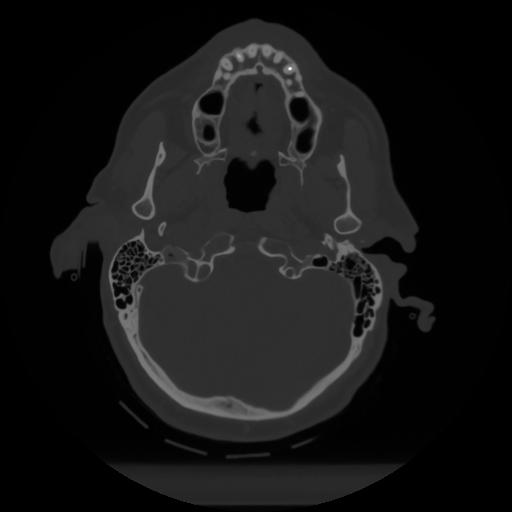

12 P.BLANDAS,,Vol,0.5,P.BLANDAS,,